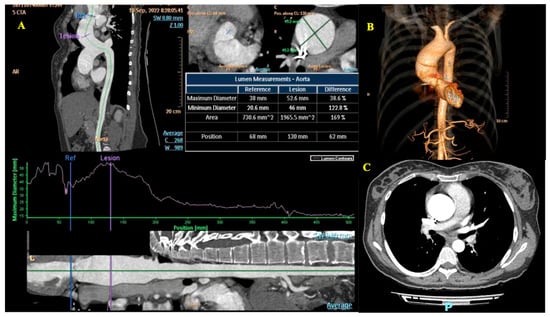

- TAVI during pregnancy, which in our case posed the potential risk of emergent conversion to surgical valve replacement due to the patient’s bicuspid aortic valve. Data from the literature also suggest some technical particularities that may occur in young women, such as femoral arteries with a small diameter and the absence of calcification on the aortic valve annulus, which could make anchoring of the prosthetic valve difficult [20].